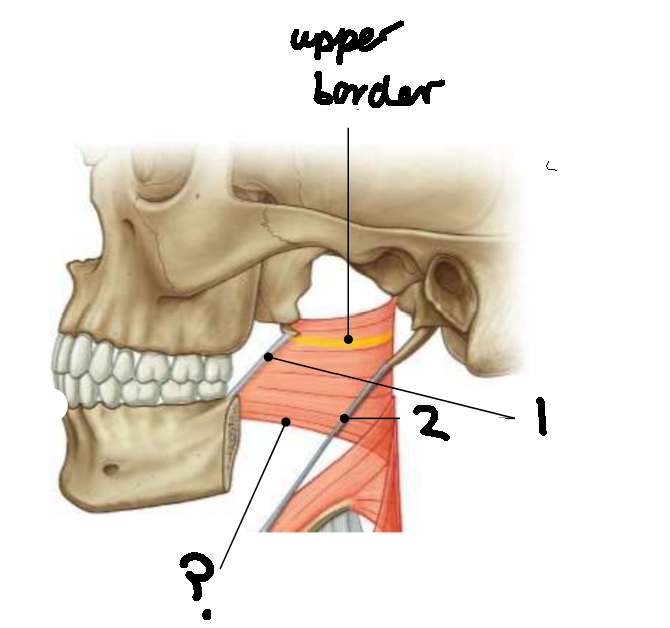

What muscle is this?

superior constrictor

What is the upper border of this muscle?

palatopharyngeal sphincter

What is 1?

pterygomandibular raphe

What is 2?

stylohyoid ligament

What are the attachments of this muscle?

pterygoid hamulus, pterygomandibular raphe, posterior end of mylohyoid line → pharyngeal raphe